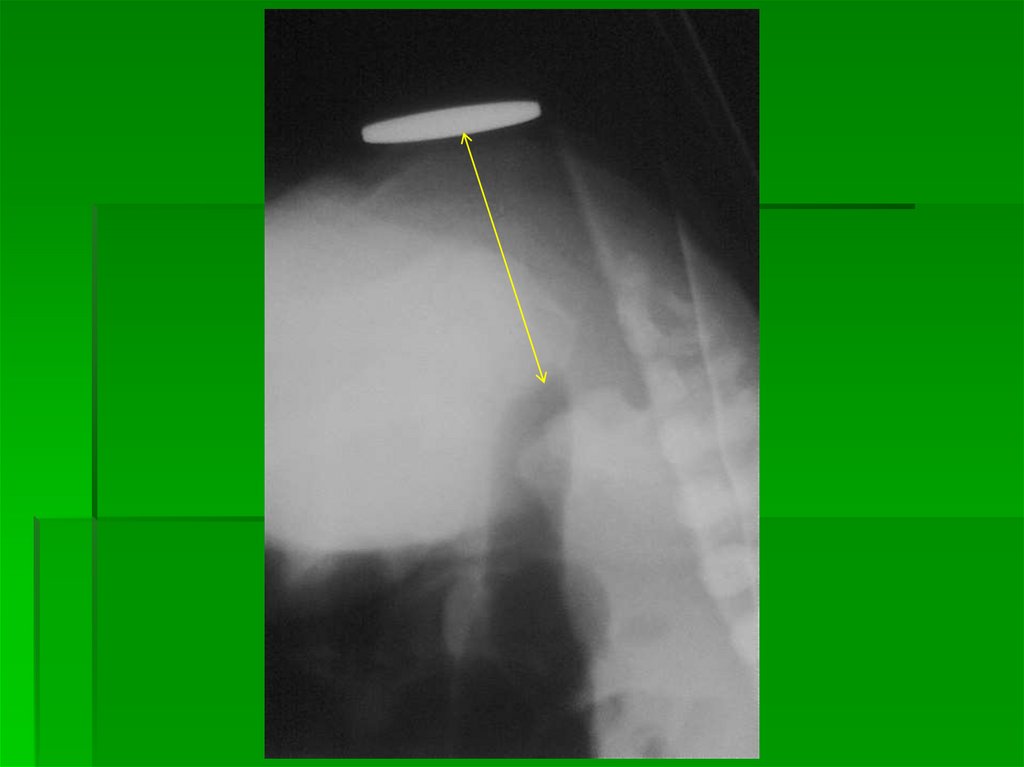

Рентгенография в прямой проекции и вертикальном положении выявляет

наличие одного или двух газовых уровней (в эпи- и мезогастрии) на фоне

отсутствия газа в остальной брюшной полости.

12.

Рентгенография в прямой

проекции и вертикальном

положении

Наличие одного или двух

газовых уровней (в эпи- и

13. КЛИНИКА И ДИАГНОСТИКА ВЫСОКОЙ СТРАНГУЛЯЦИОННОЙ КИШЕЧНОЙ НЕПРОХОДИМОСТИ.